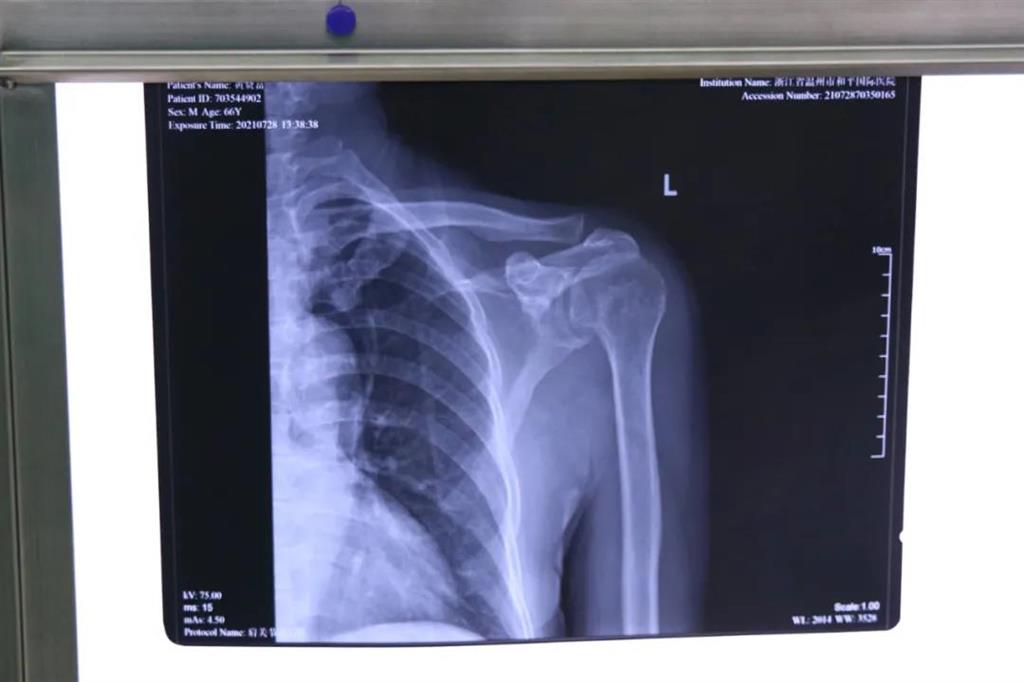

患者黃大叔(66歲)為"左肩袖損傷"病人,8年來左肩部持續(xù)疼痛伴肩關(guān)節(jié)活動輕微受限?;颊哂诮谧蠹绮刻弁醇又?,抬肩困難,難以完成穿衣服等日常生活活動。

術(shù)前檢查見左肩關(guān)節(jié)輕度腫脹,左肩關(guān)節(jié)岡上肌附著處壓痛明顯,MRI提示左岡上肌肌腱斷裂回縮,岡下肌腱部分撕裂。為此和平國際醫(yī)院關(guān)節(jié)鏡微創(chuàng)團(tuán)隊(duì)為患者制定了詳細(xì)的一期、二期手術(shù)方案。此次手術(shù)為一期肩袖成形術(shù)。

常規(guī)手術(shù)方式是傳統(tǒng)切開肩袖縫合術(shù),但缺點(diǎn)就是創(chuàng)傷較大,切口較大,術(shù)后康復(fù)困難,視野較小,難以處理其他合并傷。目前更先進(jìn)的技術(shù)是采取肩關(guān)節(jié)鏡微創(chuàng)手術(shù),術(shù)中探查肩袖撕裂口,并將其縫合固定

在和平國際醫(yī)院關(guān)節(jié)鏡微創(chuàng)團(tuán)隊(duì)的協(xié)作下,手術(shù)順利,成功用微創(chuàng)肩關(guān)節(jié)鏡進(jìn)行肩袖修補(bǔ)術(shù)。術(shù)中、術(shù)后患者幾無出血,且手術(shù)切口小,美觀,患者左肩部疼痛得到明顯緩解。